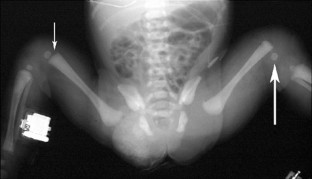

Neonatal physeal fracture of the distal femur is often difficult to diagnose. Timely and accurate diagnosis and appropriate therapy are critical in order to avoid permanent morbidity and dysfunction of the affected limb. We describe an infant in whom closed reduction and pinning were required in order to assure a good outcome.